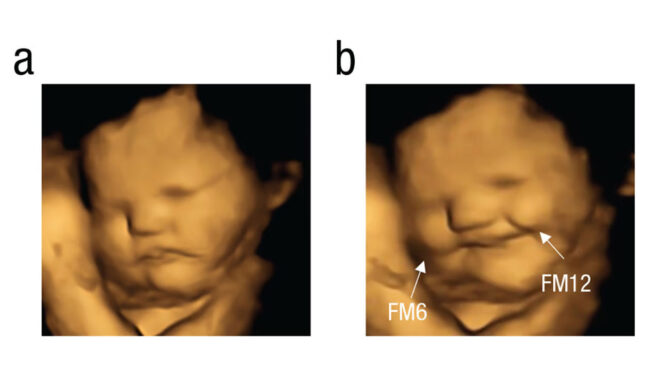

Yeni araştırma ile bu süreci yukarıda da görebileceğiniz üzere görselleştiren ve ilk kez direkt kanıt elde eden araştırma ekibi, burada uzun zamandır kullanımda olan 4D ultrason teknolojisinden yardım alıyor. 4D ultrason ile anne karnından üç boyutlu görüntü alabilen ekip, bir anne “havuç” tükettiği zaman bebeğinin gülümsediğini, “kıvırcık lahana” tükettiği zaman ise ağlıyormuş gibi bir surata geçiş yaptığını karşımıza getiriyor.

Görüntüleri anne gıdayı tükettikten 20 dakika sonra yakalayan ve gıda öncesi bir kontrol taraması da kaydeden araştırmacılar, süreçte 100 farklı hamile kadın üzerinde testler gerçekleştirmiş ve büyük oranda benzer bir sonuç elde etmiş.